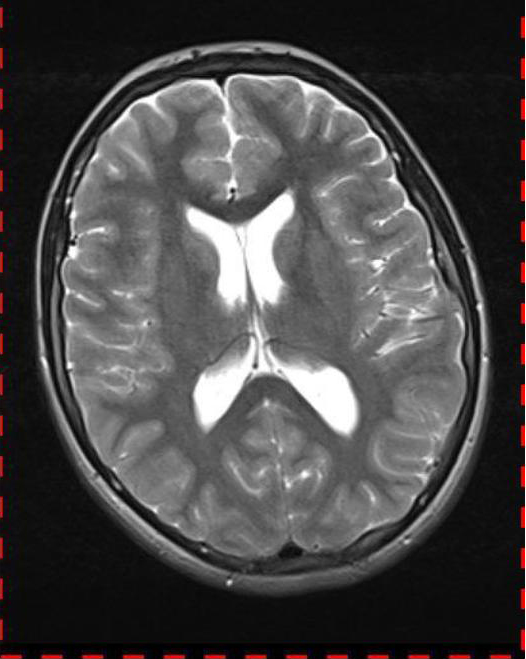

Abb. 2.2 MRT (T2 TSE transversal): obliteriertes Foramen magnum

Bei dieser Untersuchung wurde übersehen, dass die Kleinhirntonsillen in das Foramen magnum disloziert waren und eine Arnold-Chiari-Malformation mit Erweiterung des 4. Ventrikels und des Aquäduktes inklusive Kleinhirntonsillentiefstand vorlag. Bei zwischenzeitlich auswärtig erfolgtem CT der HWS wurde eine Anlagestörung im kraniozervikalen Übergang beschrieben. Eine Kontrolluntersuchung des Kopfes weitere 4 Monate später dokumentierte neben einem medullären Ödem einen progredienten Tonsillentiefstand, der zur neurochirurgischen Behandlung mit operativer Erweiterung des Foramen magnum führte.